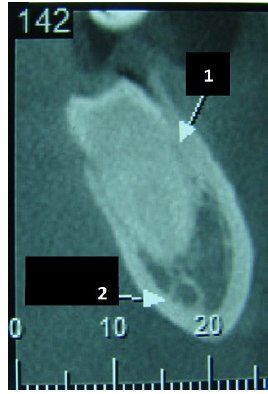

Observando a imagem abaixo, marque a alternativa que corresponde ao diagnóstico radiográfico (seta 2 ):